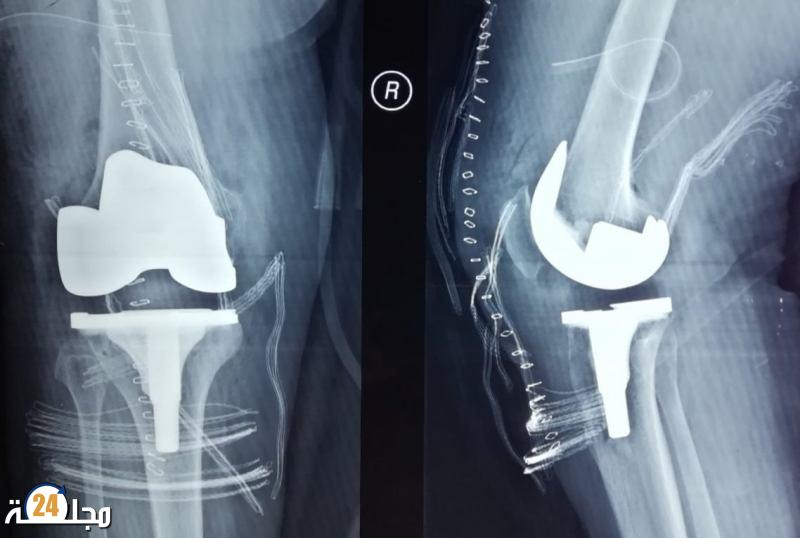

وبالعودة إلى محاكاة الطبيعة مرة أخرى، قام باحثون من جامعة إلينوي بدراسة أجنحة اليعسوب والسيكادا المقاومة للبكتيريا بغرض ابتكار مادة جديدة يمكن أن تساعد في حل مشكلات العدوى البكتيرية التي تحدث بشكل متكرر في غرسات العظام.

وفقًا للباحث الرئيسي في الدراسة أستاذ علوم وهندسة المواد في جامعة إلينوي تشينغ كاو، لم تكن هناك طريقة مناسبة للتعامل مع الالتهابات التي تصيب ما يصل إلى 10٪ من مرضى زرع العظام والمفاصل.

لذلك ابتكر كاو وفريقه البحثي طلاءً من رقائق معدنية للغرسات الطبية، يتكون من جانب واحد من عوارض نانوية مثل تلك الموجودة في أجنحة الحشرات والتي تقضي على الخلايا البكتيرية عندما تتلامس معها.

ولم يكتف الباحثون بحل مشكلة واحدة فقط مع غرسات العظام، فقد أدركوا أن طلاءهم يمكن أن يحل مشكلة أخرى وهي استكشاف مبكر لاحتمالات فشل عملية الزرع.

وقام الباحثون بتركيب مستشعرات دقيقة مرنة على الجانب الآخر من الطلاء قادرة على قياس الضغط الميكانيكي على الغرسات، التي تم وضع الطلاء عليها. يقول الباحثون إنها تسمح للأطباء بمعرفة كيف يتعافى الجسم حول الغرسة، ويمكن أن ترسل تنبيهات إذا كان الضغط على المفصل الاصطناعي أعلى من اللازم. ويعمل الباحثون في المرحلة الحالية على التوصل إلى حل لاسلكي لتوفير مصدر طاقة خارجي للطلاء.